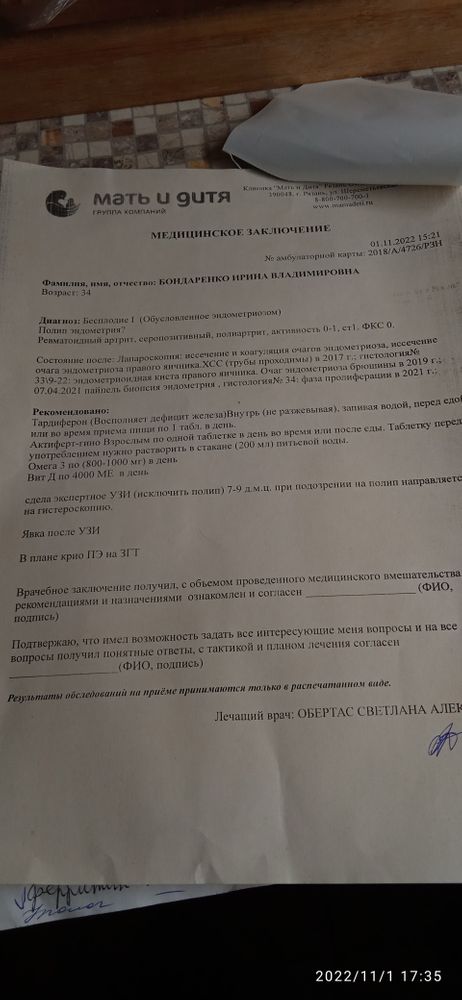

Всем здравствуйте!это просто какой-то ПИЗДЕЦ.... Такое ощущение, что просто кто то сглазил(((Не одно, то другое.Иду значит сегодня к реп, довольная, нарядная с мыслью что наконец-то в этом месяце подсадка эмбриона.И тут началось....Людей много на эко и что бухгалтерия считает баланс. И что возможно будет подсадка в следующем году. Привязалась ещё к направлению, почему где написано направление нет номера. Это просто пиз....Теперь вот надо ехать к гинекологу, чтобы она поставила какое-то там номер. 2 раза направление брала, даже и речи там не было про номер, теперь какой то номер. И тут реп решила меня осмотреть и увидела то ли как густок, то ли говорит полип.(полип исключён, я его удаляла в сентябре) И что самое интересное, она уходит в отпуск 3 ноября и говорит сделать УЗИ на 7 дц. Спрашиваю, может раньше сделать? Сказала нет. Было ли у кого так как у меня по УЗИ?Ничего не назначили? На какой день цикла вам повторно назначили УЗИ? Камера плохая, если не видно попробую ещё раз снять